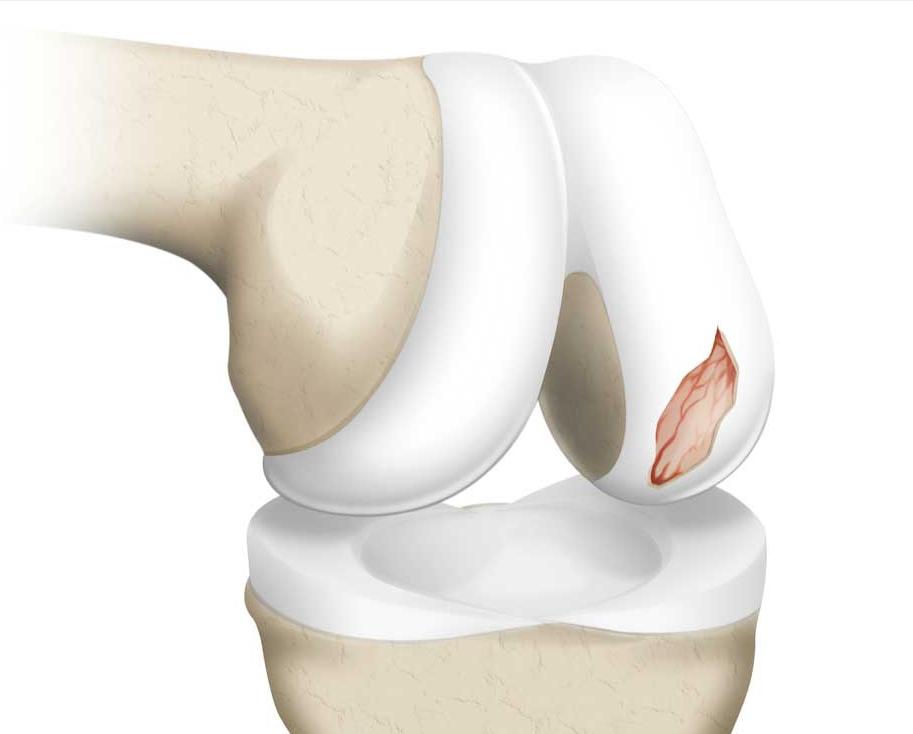

简单地解释这个桶柄状撕裂,大家可以想象成一个饼,我们把它从中间撕开两半,靠近关节腔内的这一半撕裂的半月板,就会经常在运动的过程当中造成关节的卡顿,所以小萱阿姨才会经常的出现关节的绞索。

整个手术过程是非常顺利的,总共也没有花上30分钟,在手术当中观察到小萱阿姨关节内的软骨没有发生严重的磨损,整个关节的表面是非常光滑的,但是她破裂的半月板损伤实在是太严重了,而且损伤的时间也太久,所以给她选择了部分切除成型,尽全力的保留了大部分的半月板,如果是一位二、三十岁的年轻女性,可能会尽全力的进行缝合手术治疗,但对于60岁的女性朋友来讲,身体衰弱相对来讲是比较明显的,强行进行缝合手术,很有可能造成不愈合,最终需要再次手术,这对于小萱阿姨的打击肯定会特别大。